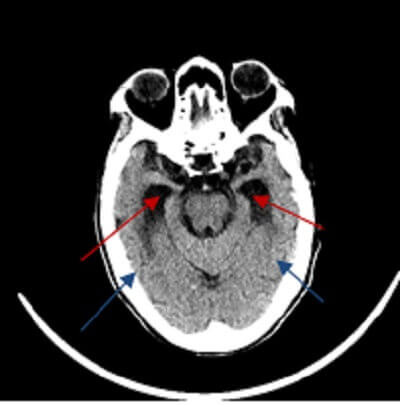

Diagnosis: Normal pressure hydrocephalus (NPH)

Figure 1: (red arrow) temporal horns of the ventricles are dilated out of proportion to sulcal atrophy, a finding suggestive of NPH.

Imaging findings suggestive of hydrocephalus include enlargement of the temporal horns, convexity to the third ventricle with distention of the anterior recess and rounded corpus callosum, flattening and effacement of the sulci and transependymal fluid in the periventricular white matter (manifested by decreased attenuation on CT and increased T2 signal on MRI).

Distinguishing NPH from ex vacuo dilation of the ventricles is a difficult imaging problem as the conditions affect similar populations. NPH is suggested when ventricular dilation is out of proportion to the prominence of the sulci, but this is a subjective call. Transependymal flow of fluid around the ventricles and corpus callosal thinning suggest NPH, as does a flow void in the cerebral aqueduct (reflecting increased velocity of CSF).